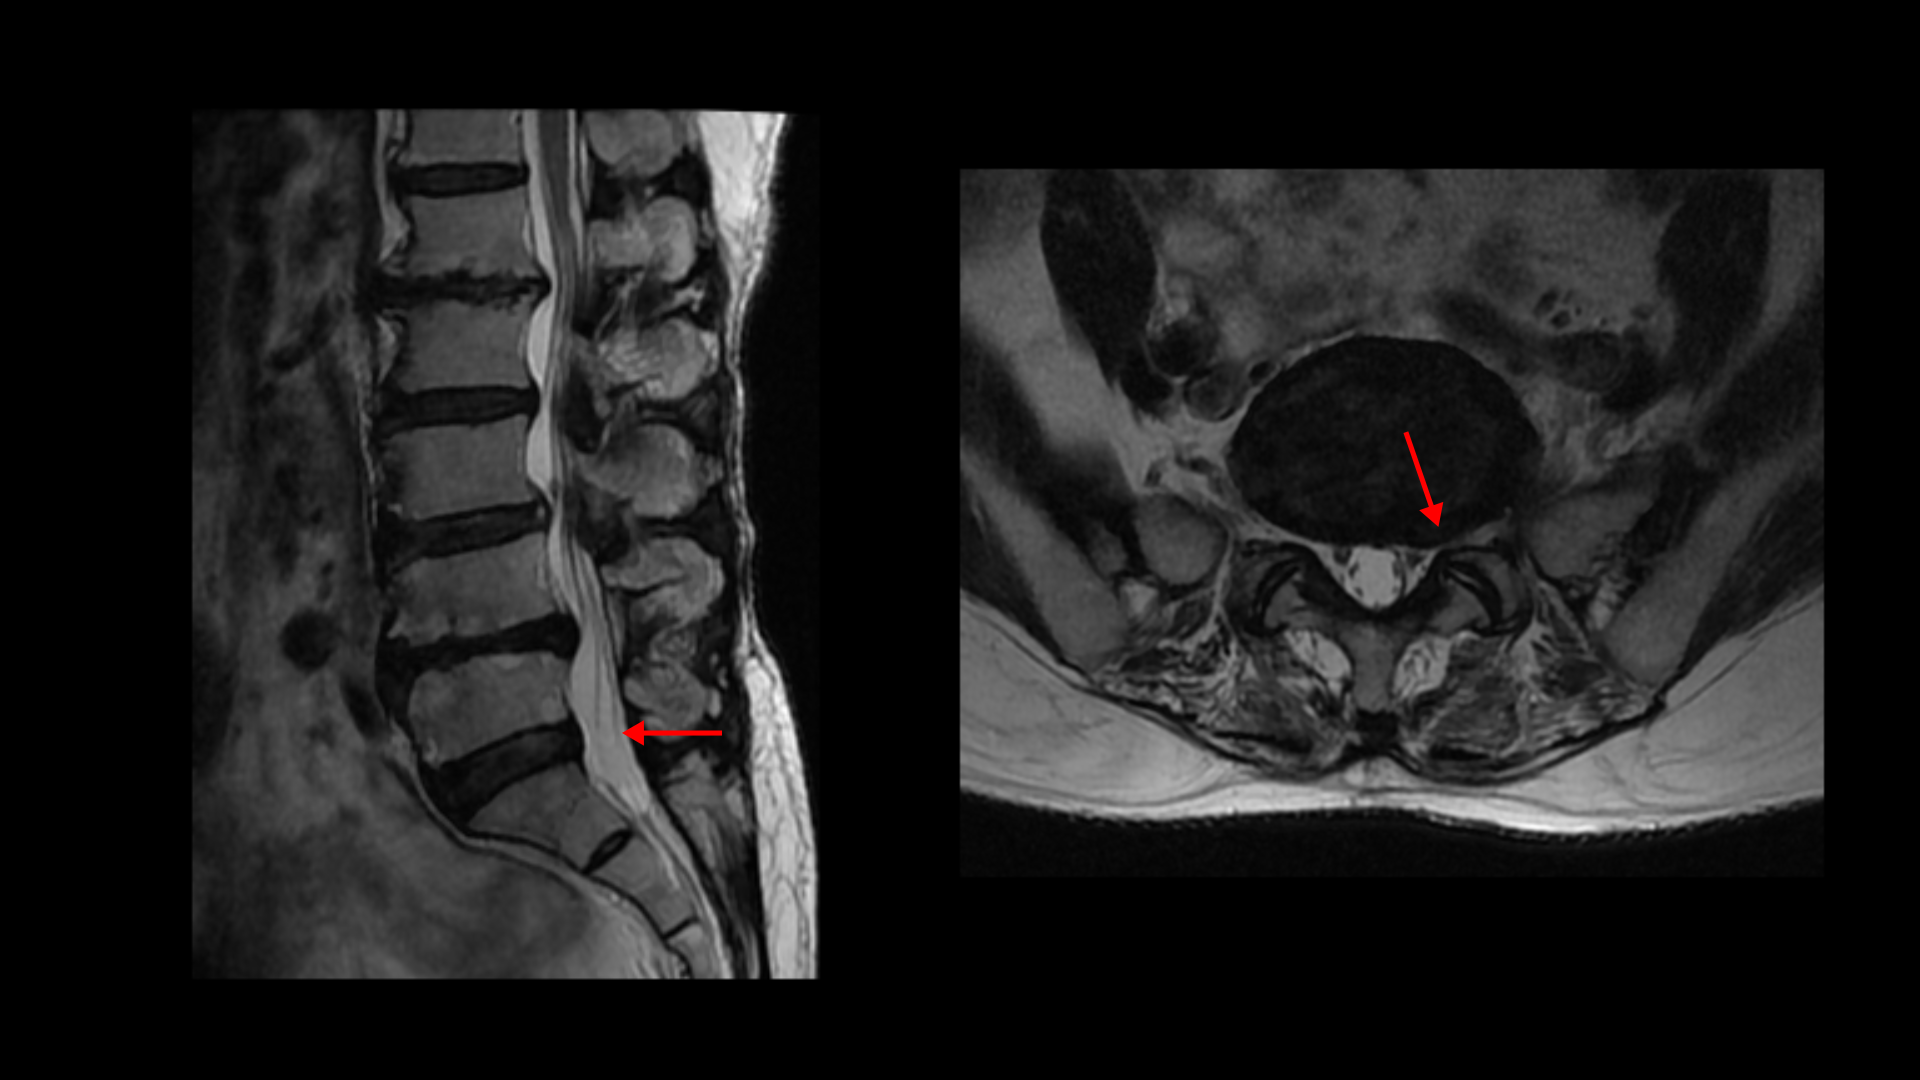

이분 MRI를 보면 허리 다섯 마디에 전부 퇴행성 디스크가 있습니다.

4-5번에는 왼쪽으로 디스크가 밀려 나와있고 심한 중심성 협착과 왼쪽 추간공협착도 있습니다.

5-1번에는 왼쪽으로 디스크가 밀려 나와있고 전반적으로 왼쪽이 상태가 더 안 좋은데 이분의 증상도 왼쪽 엉덩이와 다리의 통증과 저림 및 마비감입니다.